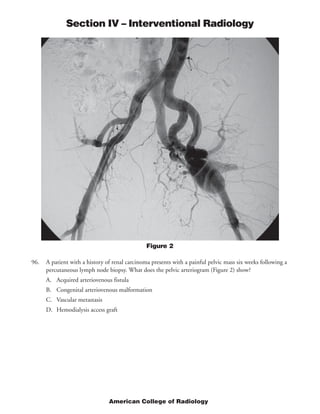

This document provides rationales for questions on the 2005 American College of Radiology Diagnostic In-Training Examination for interventional radiology residents. It includes the questions, images associated with some questions, findings for each image, and rationales for the correct answers. The questions cover topics such as locations of dialysis catheters, diagnoses for angiograms, standards for uterine artery embolization, and indications for percutaneous nephrostomy.